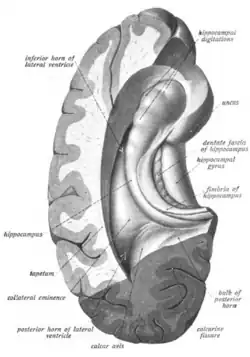

The hippocampus is a five centimeter long ridge of gray matter tissue within the parahippocampal gyrus that can only be seen when the gyrus is opened.[15][16] The hippocampus is an inward fold of three-layered archicortex (one of three regions of the allocortex) into the medial temporal lobe of the brain, where it elevates into the floor of each lateral ventricle inferior horn.[17][18][19][20] The hippocampus stretches along its anterior-posterior axis, from the amygdala to the splenium of the corpus callosum, with the head, body, and tail regions as subdivisions of this axis.[21][15] The dentate gyrus, CA subfields, fimbria, and subiculum are divisions across the short axis, the proximal-distal axis.[21]

The hippocampus, and dentate gyrus that is folded into the hippocampal archicortex have the shape of a curved, rolled-up tube. The curve of the hippocampus (known as cornu Ammonis) uses the initial letters CA to name the hippocampal subfields CA1-CA4. CA4 is in fact the polymorphic layer or hilus of the dentate gyrus, but CA4 is still sometimes in use to describe the part of CA3 that inserts between the dentate gyrus regions or blades.[17][27]

It can be distinguished as an area where the cortex narrows into a single layer of densely packed pyramidal neurons, which curl into a tight U shape. One edge of the "U" is CA4, the hilus of the dentate gyrus. This is embedded into the backward-facing, flexed dentate gyrus. In humans the hippocampus is described as having an anterior and posterior part; in other primates they are termed rostral and caudal, and in rodent literature they are the ventral and dorsal part.[28] Both parts are of similar composition but belong to different neural circuits.[29] The dentate gyrus combined with other hippocampal regions form a banana-like structure, with the two hippocampi joined at the stems by the commissure of fornix (also called the hippocampal commissure).[19][30] In primates, the part of the hippocampus at the bottom, near the base of the temporal lobe, is much broader than the part at the top. This means that in cross-section the hippocampus can show a number of different shapes, depending on the angle and location of the cut.[31]

In a cross-section of the hippocampus, including the dentate gyrus, several layers will be shown. The dentate gyrus has three layers of cells – the outer molecular layer, the middle granular layer, and the inner polymorphic layer also known as the hilus.[32] The CA3 subfield has the following cell layers known as strata: lacunosum-moleculare, radiatum, lucidum, pyramidal, and oriens. CA2 and CA1 also have these layers except the lucidum stratum.[33]